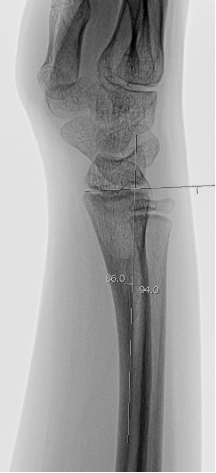

Distal radiusfyseolys <10 år flickor, <12 år pojkar (”dorsalbockad”)

Gränsvärde | ≤25º. ≤ ½ benbredd ad latus. (Mät relativt radius längsaxel på sidobild). |

Distal radiusfyseolys >10 år flickor, >12 år pojkar (”dorsalbockad”)

Gränsvärde | ≤15º. ≤ 1/4 benbredd ad latus dorsalt. (Mät relativt radius längsaxel på sidobild). |